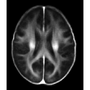

Normative myelin water atlas was created by co-registering and averaging myelin images in MNI space from 50 healthy brains to depict the population mean and variability of the myelin content in the brain. The myelin images of individual subjects were acquired using myelin water imaging. Details about myelin water imaging technique and its analysis can be found here: https://mriresearch.med.ubc.ca/news-projects/myelin-water-fraction/. The created myelin water atlas with its standard deviation can be used as a reference for your own studies related to myelin. A full description of this work can be found in this paper: https://www.ncbi.nlm.nih.gov/pubmed/31347238.

• Myelin water imaging

• Atlas for normal myelin content